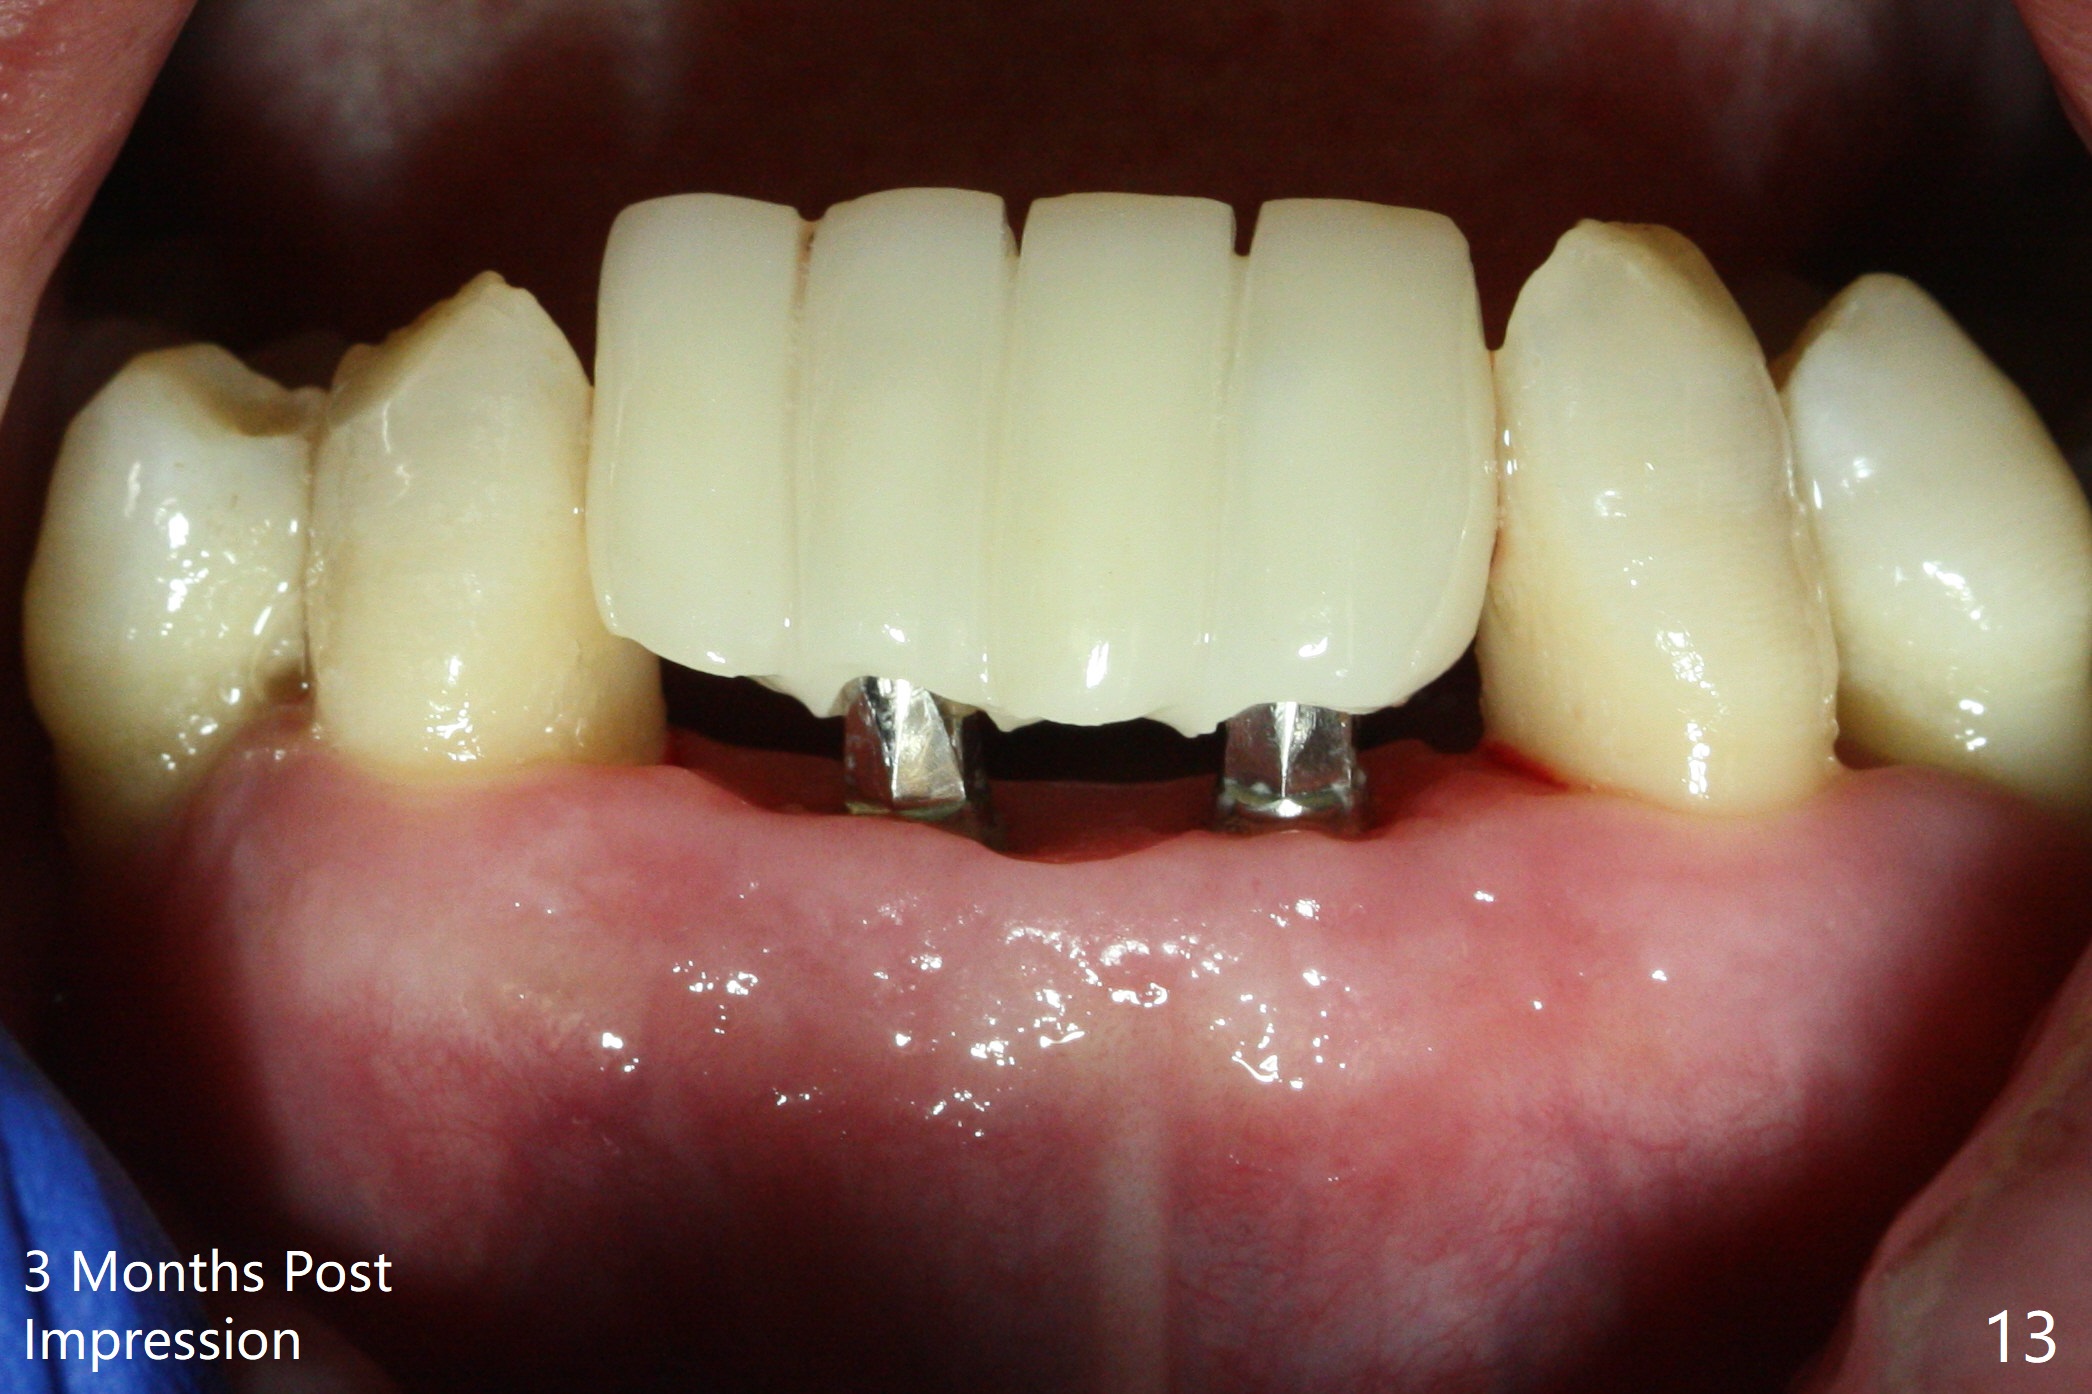

After extraction of 4 of the lower incisors, there are basically 2 sockets (#23/24 and 25/26), separated by the apparently midline bone (Fig.1 red line). In spite of using Lindamann bur to move the 25/26 osteotomy mesially, a 3x14(2) mm dummy implant remains close to the tooth #27 (Fig.2). The terminal branch of the Incisive Canal (<) is located between the lateral and central incisors. A de novo osteotomy (Fig.3 (1.5 mm drill)) is made mesial to the original one (O). While the 3x14(2) mm dummy implant is incompletely placed at #25/26, a 3x14(4) mm 1-piece one is placed at #23/24 (Fig.4). Finally the same implant is placed at #25/26 with placement of mineralized cortical/cancellous bone (Fig.5 *). When the large sockets are sutured, the supraerupted teeth #7-9 touch the lower gingiva (Fig.6). The incisal edge is reduced for clearance (Fig.7). Periodontal dressing is less likely to be dislodged with the incisal edge reduction (Fig.8,9). A provisional FPD is fabricated 1 week postop. Hard (Fig.10) and soft (Fig.11,12) tissues heal 5.5 months postop. The patient returns for crown cementation 3 months post impression (9 months postop, Fig.13,14).